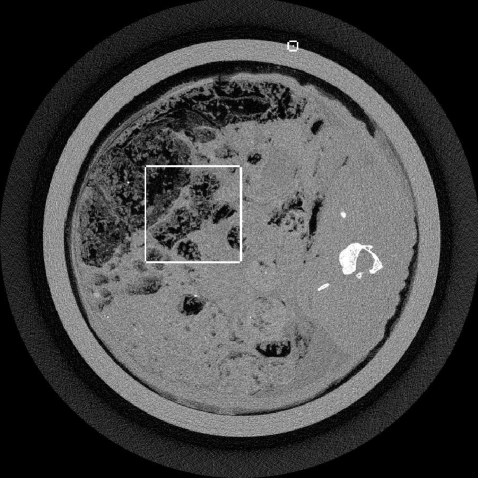

The up-sampling and frequency constrained ASD-POCS algorithms are demonstrated with an XCounter CT scan of a rabbit with a thin wire taped to the outside of the sample holder. The data are low-intensity and contain 1878 projections with a 2266x64 bin detector at a resolution of 0.1 mm. The thin wire provides a good resolution test for the image reconstruction algorithm. For the present purpose, we take the middle row on the detector from this data set and focus on 2D fan-beam CT reconstruction with 1878 projections on a 2266-bin linear detector array.

An FBP image of this data set is shown in Fig. 1, where some regularization is performed by Gaussian smoothing with a window 2 pixels wide. The rectangles indicate the regions where comparisons of the different algorithms are shown. Comparisons for each algorithm will be made at a level of image regularization where each image’s TV-norm is an eighth of that of the unregularized FBP image. The images are shown just to give a sense about the behavior of the algorithms; more rigorous evaluation with different levels of regularization will be performed in future work.

We illustrate the problems with employing a matched-resolution grid, 10241024, and a very high resolution grid, 40964096, with the basic ASD-POCS algorithm. The pixel width is 0.1 mm for the former grid and 0.025 mm for the latter. Note that the rabbit support projects onto the middle 1000 bins of the full projection. The FBP image is shown on a 40964096 grid, but because FBP is based on an explicit inverse its pixel values are not affected by the grid size. In Fig. 2 the matched grid clearly leads to a loss of resolution relative to FBP, because the image is forced to be uniform over the 0.1mm 0.1mm squares. Simply going to a larger array does improve the ASD-POCS image, but the noise pattern shows additional false structure when compared with the FBP image. These structures arise from the fact that the imaging problem is under-sampled by roughly a factor of ten and this under-sampling occurs in both view-angle and detector-bin directions. The random, sparse specks that appear could be confused with micro-calcifications in the context of breast imaging.